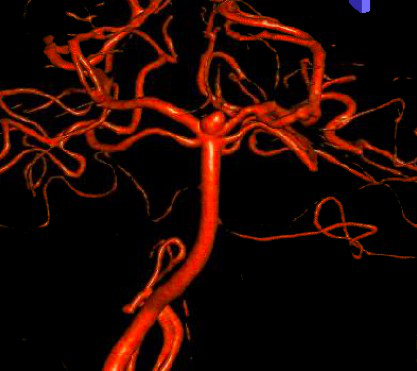

三维脑血管造影示基底动脉瘤。